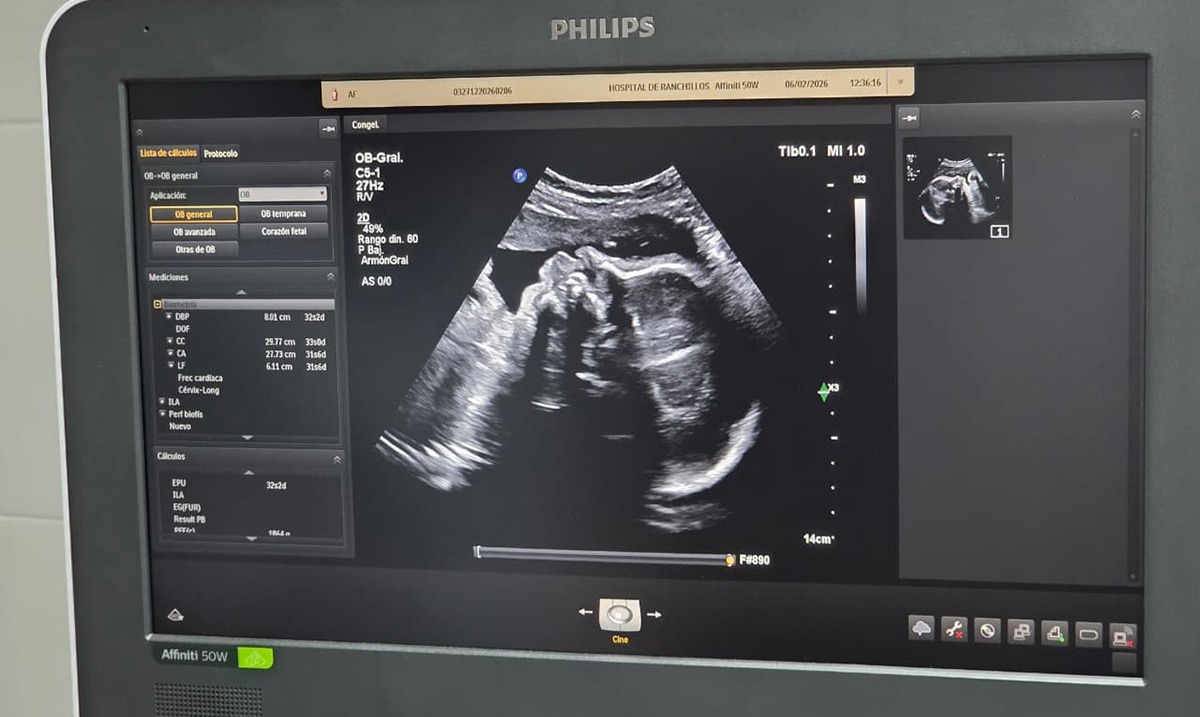

Durante la reunión se trabajó sobre la puesta en funcionamiento del ecógrafo recientemente incorporado, la organización del servicio y la planificación del trabajo en red, haciendo hincapié en la detección precoz de embarazos de riesgo que requieran intervención o seguimiento continuo en el área operativa este.

En ese sentido, la licenciada Vilma Carrizo destacó que esta incorporación permitirá ordenar el servicio de acuerdo con los requerimientos de la tecnología disponible y profundizar acciones de prevención. “Esta tecnología nos posibilita detectar patologías que pueden presentarse durante el embarazo en relación con el feto y actuar de manera oportuna con medidas preventivas”, señaló.

Por su parte, el responsable del servicio de ecografía, doctor David Núñez, expresó su satisfacción por la incorporación del nuevo equipamiento y el fortalecimiento del equipo de medicina materno fetal. “En medicina la tecnología es fundamental cuando se complementa con recursos humanos capacitados. Gracias al Ministerio de Salud contamos con un equipo de última generación que utilizamos en beneficio de la población”, remarcó.